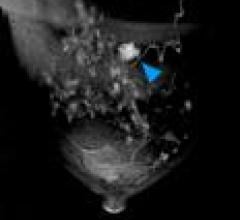

April 7, 2010 - A dual-modality tomographic (DMT) breast scanner, developed by researchers at the University of Virginia Health System (UVA), in a pilot study pinpointed to a much finer degree than mammography, ultrasound, MRI and even a needle biopsy, the location of breast masses and more accurately distinguished between cancerous and harmless lesions.